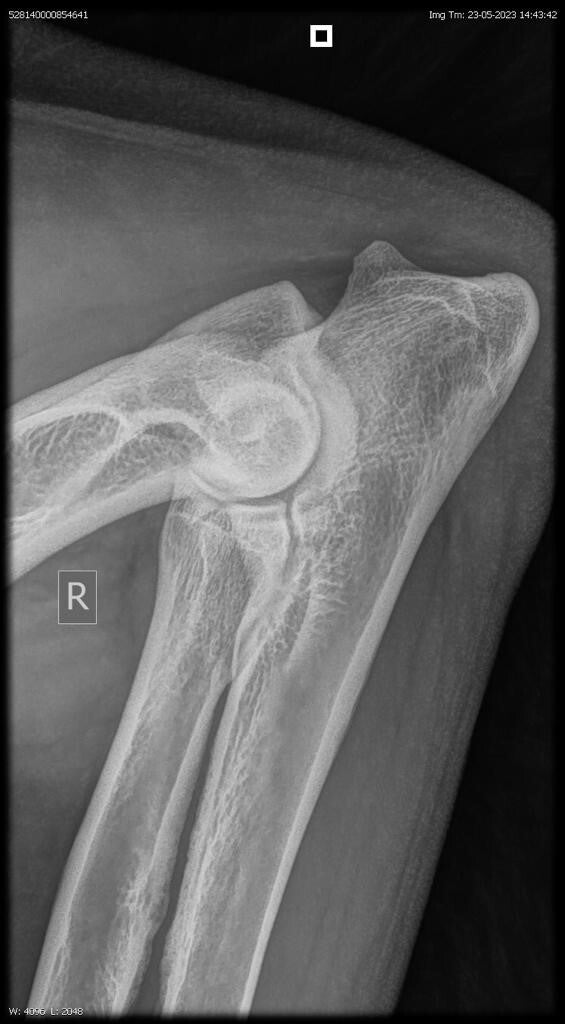

23/06/2023: Röntgenopname ellenbogen + heupen -> geen afwijkingen (heupdysplasie A, ED vrij)